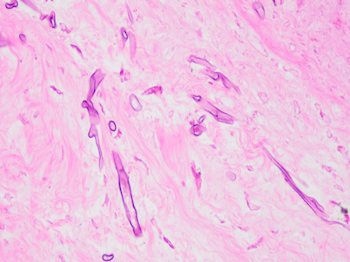

Case History:

40 year old male found unresponsive. No medical or social history. The scene was unremarkable. External examination revealed scars on the forearms and legs. Autopsy revealed 450 g heart, edematous lungs, and firm liver.